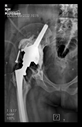

The radiological examination allowed us to verify the close bone-to-implant contact and the unchanged position of the implant during follow-up.

In all the cases operated with the above-described targeting procedure, the stems of the cups remained between the cortical bone surfaces without perforation of the linea terminalis, as shown by postoperative radiographs. There were no complicated surgical situations. In 16 cases, the wound healings were uneventful, and the hips were able to bear weight again after postoperative rehabilitation.